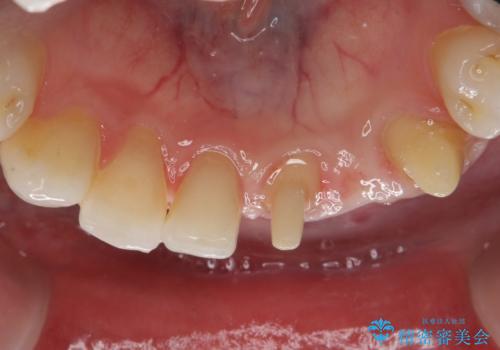

- 他院にて矯正治療を行ったが、左下の前歯の見た目が気になるのでセラミックで治したいといらっしゃった方の症例です。

左下123番のブリッジになるが、左下1番と3番の歯軸が合っておらず神経治療が必要になる可能性があるため部分矯正を提案したところ、希望されなかったため、そのままの歯軸でオールセラミッククラウンによる補綴を行いました。